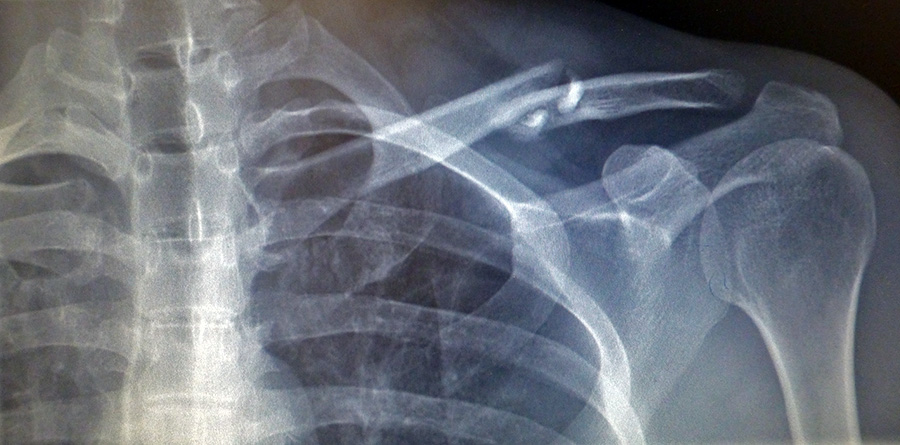

a friendly woman came out and brought me into one of the exam rooms. i was already in a foul mood so made no effort to reciprocate her hospitality. after some more waiting, an attending physician came in to talk with me. he showed me my x-rays. he said ideally he'd look to see more healing, which hasn't happened yet, and that i might have to come back in another 6 weeks just to make sure everything was okay. regardless of what you can and can't see from the x-rays, i feel fine myself. i have full articulation of my shoulder and arm now with just a little soreness, and if i had to put a number on it, i'd say i'm probably 85% healed. i also asked about the bump. he said that was normal, that it'd go down over time, but there'd always be a small bump there. he also told me my clavicle would be about a centimeter shorter than before, which gave me some concerned, but said my body would naturally adjust and i wouldn't know the difference.